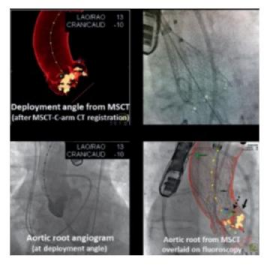

Fusion imaging –

- 3D picture of the heart (from a CT scan or ultrasound) is overlaid onto the live X-raycreating a “roadmap” showing the exact, 3D anatomical structure of the heart, with the catheters moving inside it, on a single screen.

Benefits: Fusion imaging allows the cardiac team to work with greater confidence andaccuracy, making complex procedures like TAVI, MitraClip, LA appendage closure safer and faster for the patient with outstanding results.